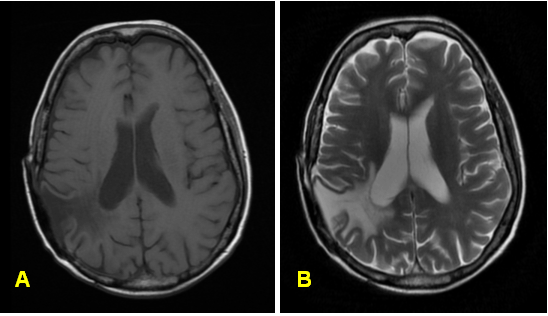

The patient did well during follow-up until 1999, when he was admitted for fatigue, weight loss and shortness of breath and was found to have lymphadenopathy. Subsequent imaging, blood analysis and biopsy confirmed the diagnosis of stage IV non-Hodgkin's lymphoma. He was then treated with CHOP systemic chemotherapy and went into remission. In March 2011, he presented to our emergency department with acute shortness of breath and a workup revealed acute mitral regurgitation as the underlying cause. During his stay at our facility, multiple pulmonary nodules were discovered on chest radiogram (Figure 1) and computed tomography (CT) scan showed multiple multilobar lung masses, measuring up to 8.4 cm x 5.3 cm. Magnetic resonance imaging (MRI) of the brain showed recurrent versus residual meningioma (Figure 2)– however this was not further biopsied. A left upper lobe nodule fine-needle aspiration revealed metastatic malignant meningioma via light microscopy (Figure 3) and immunohistochemistry staining (Figure 4). A surgical resection was indicated because of the doubling of one of the lung masses (RLL nodule from 3 cm x 3 cm to 3 cm x 6 cm in less than twelve months), in order to confirm the diagnosis. Again, metastatic malignant meningioma was confirmed by biopsy. PET scan showed multiple hypermetabolic lesions throughout the lung. Unfortunately, soon after, the patient deteriorated after developing mitral valve endocarditis and died from multi-system organ failure.

Figure 1: (A) Chest roentgenogram shows multiple pulmonary nodules, two in the right and two in the left lung lobes (marked off with measurements), (B) The chest computed tomography showing multilobar lung masses during a CT-guided fine needle aspiration of a right posteriomedial pleural mass.

Figure 2: Imaging of malignant meningioma. (A) Transverse magnetic resonance imaging T1-weighted postgadolinium image followed by, (B) Transverse T2-weighted postgadolinium image showing postsurgical changes status-post parietal-occipital craniotomy with extensive encephalomalcia (softening of cerebral tissue) and old hemorrhage in the right parietal region. Lobular tissue extending along the posterior falx presumably related to the patient's history of meningioma, suggesting residual/recurrent tumor.